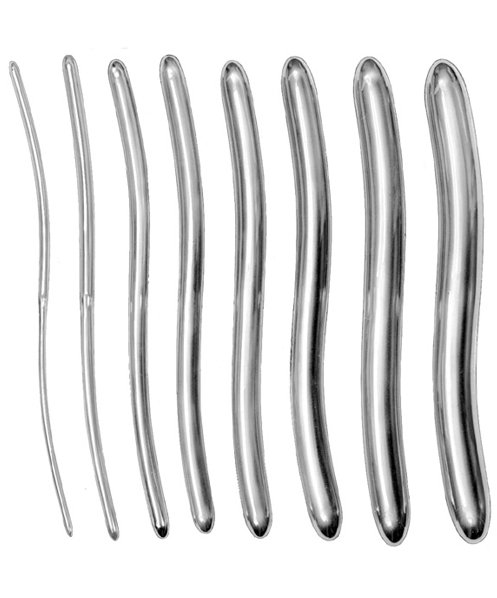

- Surgical Instruments, Urology

Gall Duct Dilator

- Size : 21 CM - 8 1/4"

- Read more

-

- Surgical Instruments, Urology

Gall Duct Dilator

- Size : 21 CM - 8 1/4"

- Read more

-

- Surgical Instruments, Urology

Gall Duct Dilator

- Size : 32 CM - 12 1/2"

- Read more

-

- Surgical Instruments, Urology

Gall Duct Dilator

- Size : 32 CM - 12 1/2"

- Read more

-

- Surgical Instruments, Urology

Gall Duct Dilator

- Size : 32 CM - 12 1/2"

- Read more

-

- Surgical Instruments, Urology

Gall Duct Dilator

- Size : 32 CM - 12 1/2"

- Read more

-

- Surgical Instruments, Urology

Gall Duct Dilator

- Size : 32 CM - 12 1/2"

- Read more

-

- Surgical Instruments, Urology

Gall Duct Dilator

- Size : 32 CM - 12 1/2"

- Read more

-

- Surgical Instruments, Urology

Gall Duct Dilator

- Size : 32 CM - 12 1/2"

- Read more

-

- Surgical Instruments, Urology

Gall Duct Dilator

- Size : 32 CM - 12 1/2"

- Read more

-

- Surgical Instruments, Urology

Gall Duct Dilator

- Size : 32 CM - 12 1/2"

- Read more

-

- Surgical Instruments, Urology

Gall Duct Dilator

- Size : 32 CM - 12 1/2"

- Read more

-

- Surgical Instruments, Urology

Gall Duct Dilator

- Size : 32 CM - 12 1/2"

- Read more